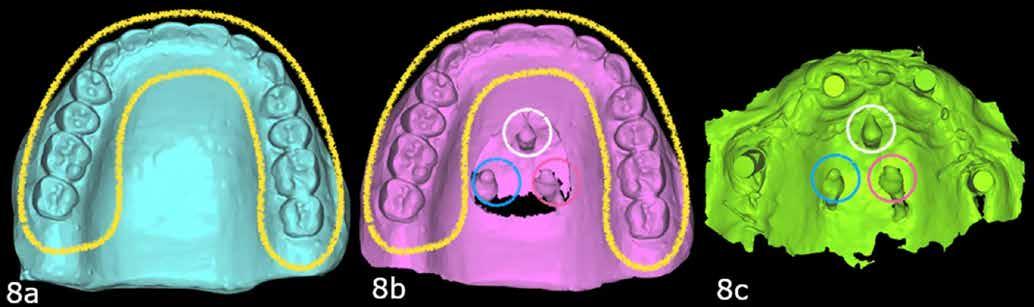

7. a–b ábrák: Az implantátumok ideiglenes fejei és az azonnali ideiglenes koronák okkluzális nézetből. – 7. c ábra: A bal felső második premoláris ideiglenes koronája. – 8. a–c ábrák: Hagyományos, zárt kanalas lenyomatvétel A-szilikonnal a jobb felső 4–6 implantátumok lemintázására. – 9. a–c ábrák: Hagyományos, zárt kanalas lenyomatvétel A-szilikonnal és folyékony kompozittal.

A végleges protetikai ellátást három hónappal az implantációt követően kezdtük meg. Az implantátumok gyógyulása panasz- és tünetmentes volt. Hagyományos, zárt kanalas A-szilikon lenyomatot vettünk (8. a–c ábrák). Egy esetben a gingivális emergenciát sikerült nagy pontossággal lemintázni fényre kötő folyékony kompozit segítségével (Master Flow, Biodinamica; 9. a–c ábrák). Három lítium-diszilikát és egy monolitikus cirkonkorona készült (10. a–b. ábrák), amelyek cementtel rögzültek a végleges protetikai fejeken (Dual RelyX™ U200, 3M; 11. a–b ábrák).